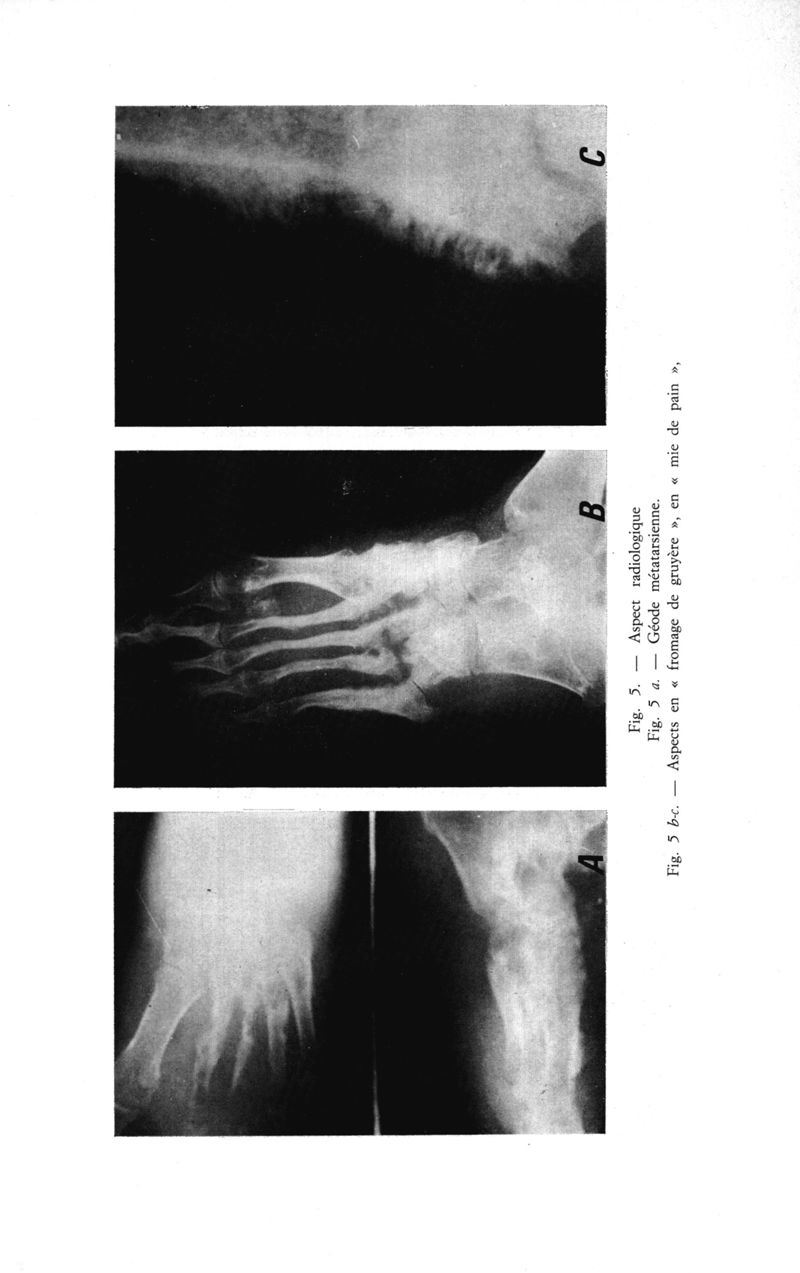

Médecine tropicale: revue française de pathologie et de santé publique tropicales

. - Marseille, 1974.